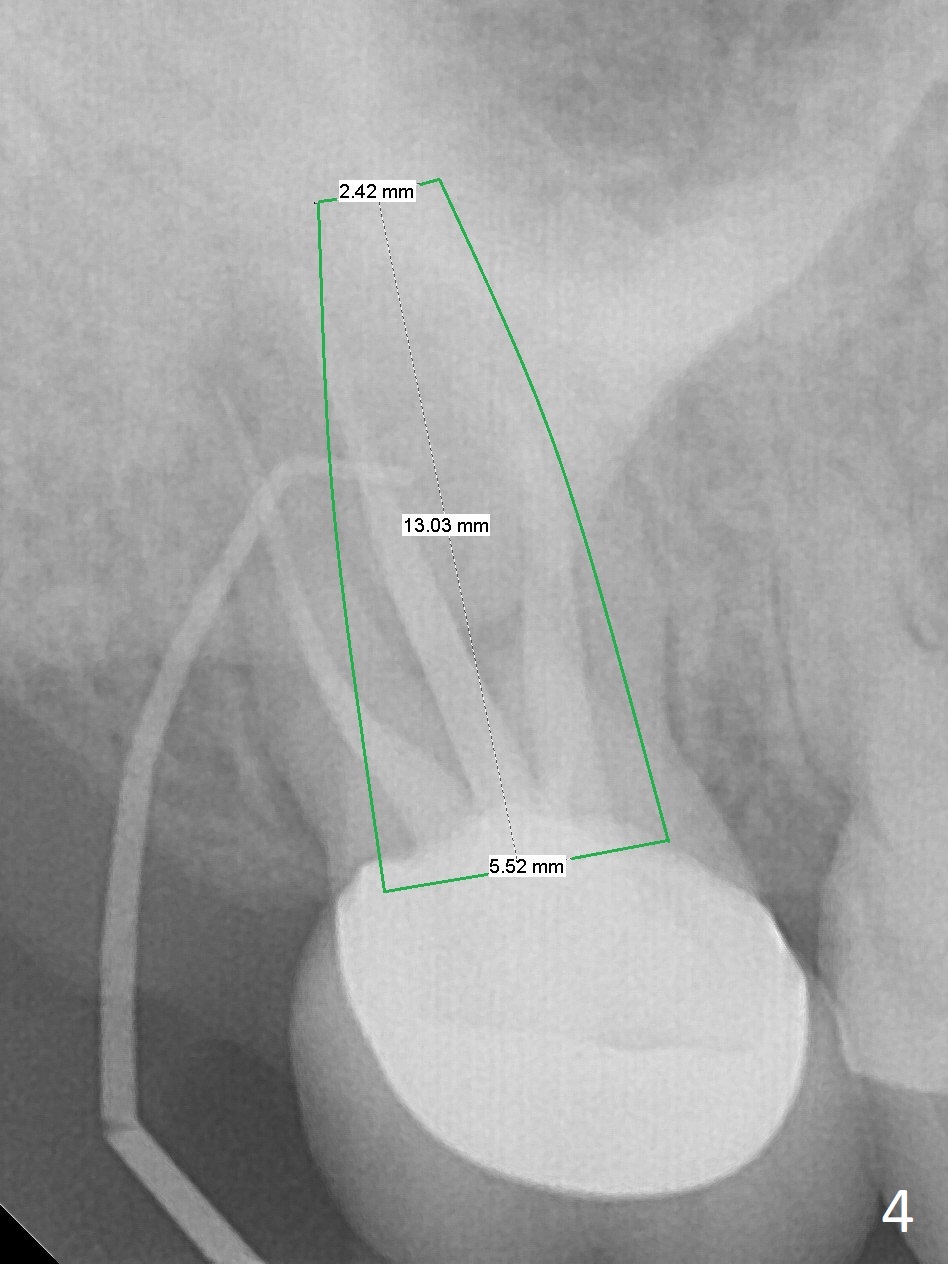

A 58-year-old woman has had RCT done at #2 for several years. The roots are trifurcated with sufficient bone height (Fig.1-3). Recently the tooth becomes symptomatic with formation of a distal fistula (Fig.4). After extraction, the septum (Fig.5 S) may be wide enough for initial drill (Fig.6). If not, resection the thin part of the septum (Fig.7 red line, with small or medium Rongeur) and use the initial drill (Fig.8). Anyway, take PA immediately to avoid sinus membrane perforation. If possible, adopt single drill technique.